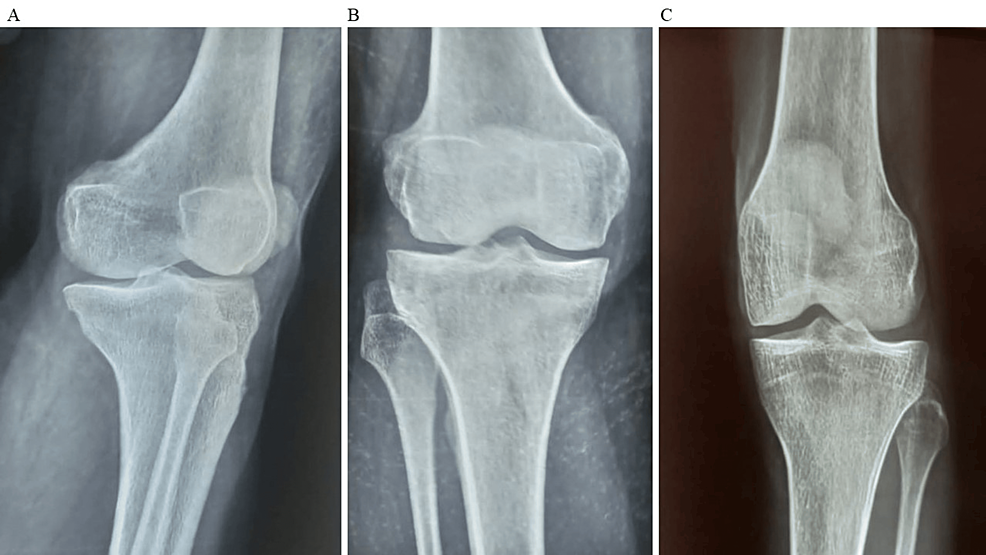

平均WOMAC評(píng)分從基線時(shí)的56.8±11.5下降到六個(gè)月時(shí)的41.2±10.6。此外,還監(jiān)測了不良事件的發(fā)生情況,報(bào)告了七起不良事件,占參與者的28.0%。這些發(fā)現(xiàn)強(qiáng)調(diào)了該治療在六個(gè)月內(nèi)減輕疼痛和改善功能結(jié)果方面的有效性。下圖2顯示了開始干細(xì)胞治療后骨骼的側(cè)視圖和前后視圖。?

圖3和表3顯示了六個(gè)月隨訪的治療結(jié)果,展示了各種結(jié)果測量值及其相應(yīng)的p值。對(duì)于VAS(一種評(píng)估疼痛強(qiáng)度的指標(biāo)),參與者的疼痛從基線到六個(gè)月顯著減輕。基線時(shí),平均VAS評(píng)分為7.4±1.1,六個(gè)月時(shí)降至 5.2±1.5。基線和六個(gè)月之間的平均VAS評(píng)分差異具有統(tǒng)計(jì)學(xué)意義(p<0.05),表明疼痛程度明顯改善。

同樣,如圖4中評(píng)估疼痛、僵硬和身體功能的WOMAC所示,參與者表現(xiàn)出了顯著的改善。平均WOMAC評(píng)分從基線時(shí)的56.8±11.5下降到六個(gè)月時(shí)的41.2±10.6,觀察到統(tǒng)計(jì)學(xué)上顯著的差異(p<0.05)。